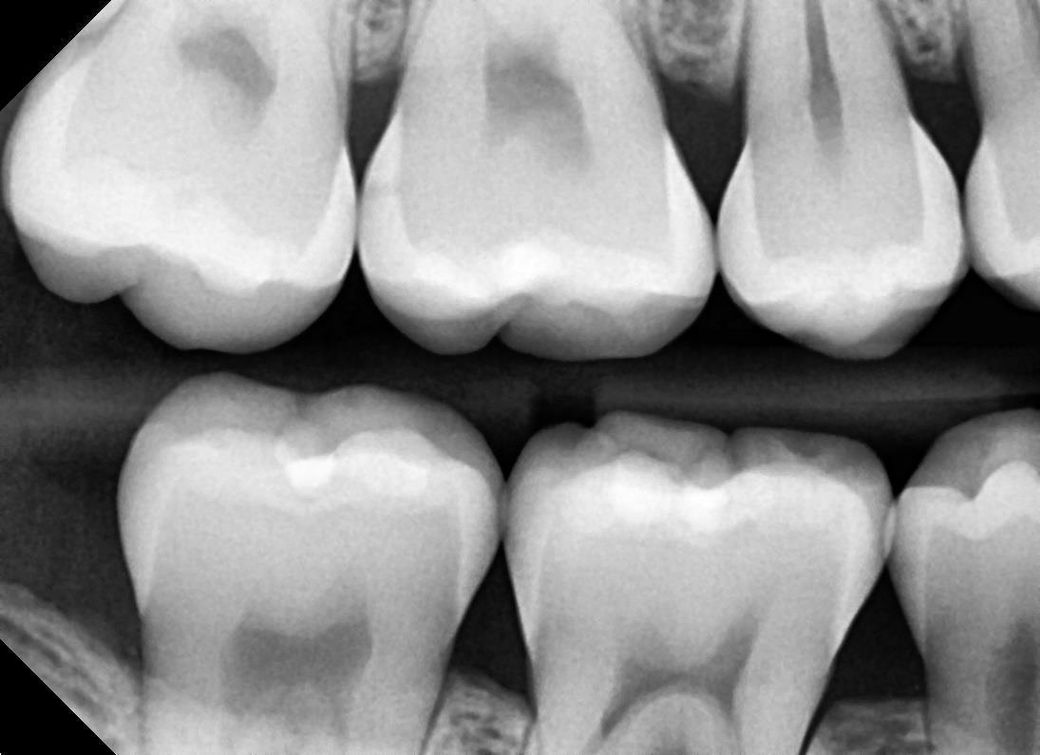

치과에서 인접면충치 진단받았습니다. 치료해야 할까요?

법랑질 쪽 충치 초기 진단은 2년 전에 받았었는데

이번에 xray찍어보니 다른쪽은 괜찮았던 반면

오른쪽 윗 끝 어금니 부분 인접면 충치가 확장되어 법랑질이 뚫렸다고 합니다

• 1번 째 사진